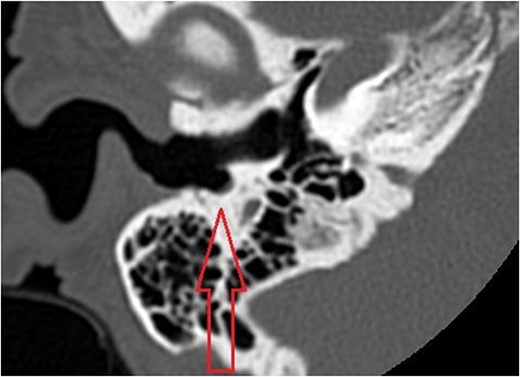

The patient evaluation and the data collection of this rare entity were performed in the senior author’s Otolaryngology practice in Poplar Bluff Regional Medical Center, Poplar Bluff, Missouri, USA (Table 1). Patient A, a 72-year-old female, was initially seen in 06/2015 and has been consistently followed for 87 months. On initial evaluation, the unusual clinical presentation triggered a workup with a CT of the temporal bone (Fig. 1), revealing a minor area of cortical erosion in the inferior wall of her right bony external auditory canal. Her initial presenting complaint was cerumen impaction on the right side associated with same side hearing loss. The patient has no history of diabetes, is treated with estradiol and progesterone tablets for hormonal replacement therapy and has no diagnosis of osteoporosis. Her blood pressure medications include atenonol and triamteren and has been on the same medications for the last seven years of our observation. The patient was managed with serial external auditory canal debridements, every 6 months. She had no history of otitis externa during the years of follow-up. Photographic documentation in her most recent visit (10/2022) revealed healthy appearing healthy mucosalization of the cavity and minimal amount of ceruminous debris (Fig. 2).

Right external auditory canal on patient A demonstrating excellent mucosalization of the indentation in the inferior aspect of the external auditory canal after serial cerumen debridement procedures in the office.